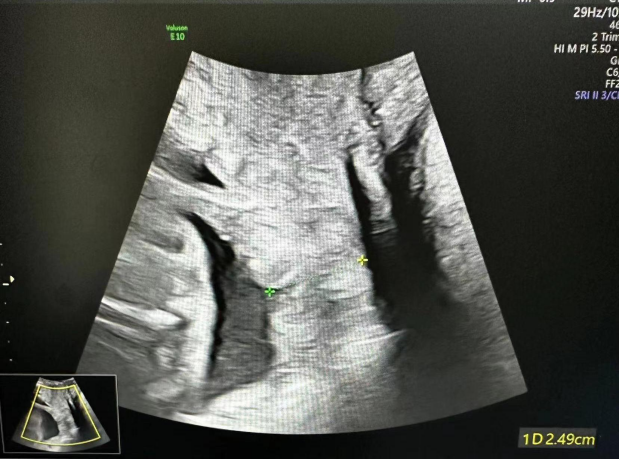

术前宫颈中上段呈U形,下段有效宫颈管长约0.67cm

术后有效宫颈长约2.9cm